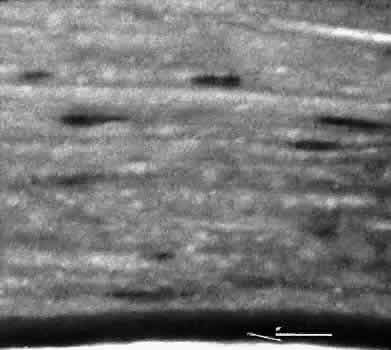

A flat anterior chamber is characterized by anterior displacement of the iris to near or in actual contact with the posterior surface of the cornea. The most common cause is leakage of aqueous along one of the suture tracks. Prolonged decompression of the anterior chamber increases the risk of synechiae formation and intractable secondary closed-angle glaucoma. Corneal endothelial damage may result in bullous keratopathy. Choroidal edema (choroidal hydrops or detachment) (Fig. 31) may be associated with a flat anterior chamber and may potentiate the condition. The choroidal edema will slow or stop aqueous production by the ciliary body, further delaying reformation of the anterior chamber. The histologic characteristics of choroidal edema consist of spreading of the choroidal tissue in a fanlike configuration and eosinophilic fluid filling the intervening spaces. The edema fluid may be lost in processing, leaving multiple apparently empty spaces.

Fig. 31. A case of choroidal detachment. A. By fundus reflex, a large dome-shaped mass can be seen originating from the choroid. The differential diagnosis would include uveal malignant melanoma. In this case, the clinical findings were due to choroidal detachment from the sclera because of fluid accumulating in the suprachoroidal space following cataract surgery. B. The histologic section from another case of choroidal detachment illustrates the location (arrow) and extent of the detachment. In this case the detachment extends to the region of the ciliary body limited anteriorly by the attachment of the choroid to the scleral spur. The displacement of the ciliary body will result in apparent shallowing of the anterior chamber. (Hematoxylin-eosin stain; × 6.)